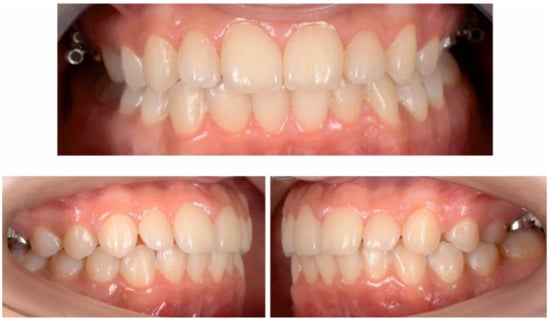

2.3. Treatment Progress

2.3.2. Second Phase of Treatment—2017—Bite-Blocks and Transpalatal Arch

3. Results